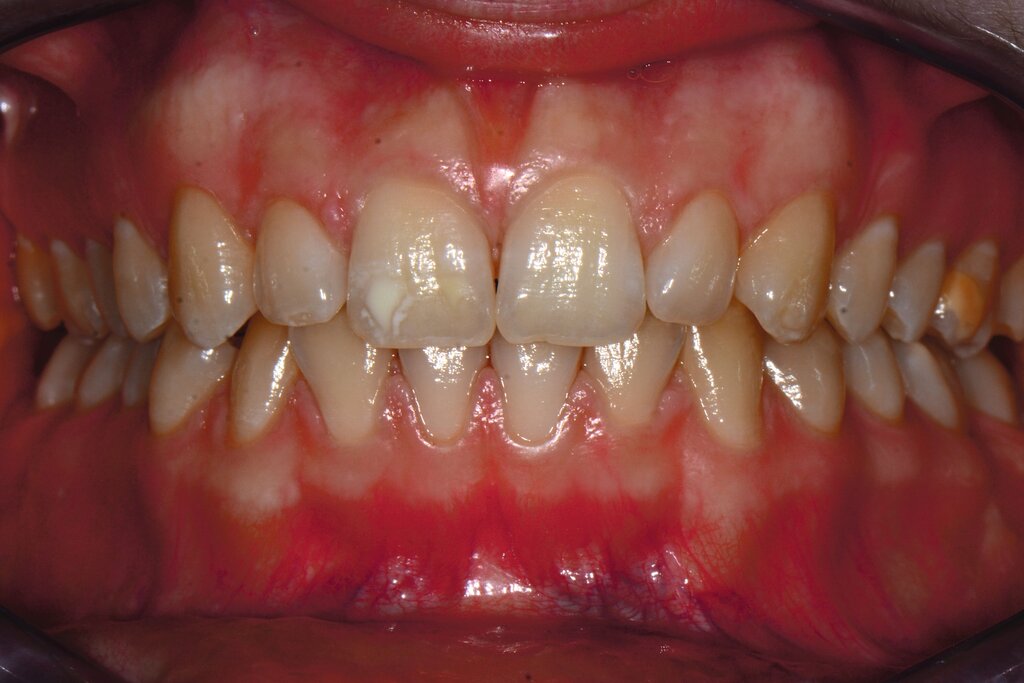

Das klinische Erscheinungsbild an bleibenden Zähnen zeigt typischerweise weißlich-gelbe bis gelblich-braune Opazitäten, die zumindest in einigen Bereichen durch eine scharfe Abgrenzung (engl.:„demarcated opacities“) zum gesunden Zahnschmelz charakterisiert sind (Abbildungen 3 und 4). Die abgegrenzten Hypomineralisationen befinden sich mehrheitlich im Bereich der inzisalen Kronenhälfte unabhängig von dem Auftreten an Front- oder Seitenzähnen. Die Ausprägung am Zahn kann dabei auf einzelne Areale oder Höcker begrenzt sein.

Bei einer schwerwiegenderen Ausprägung sind Zahnflächen vollständig betroffen, mitunter alle Zahnflächen an einem Zahn. Die Verteilung in der Dentition beziehungsweise an den Indexzähnen ist gleichermaßen variabel und betrifft nicht nur die Defektgröße, sondern auch die Farbe und Festigkeit. Was die Festigkeit betrifft, gilt als die Faustregel: Je dunkler die Farbe des Schmelzes, umso weicher beziehungsweise poröser und damit minderwertiger wird dessen Qualität sein. Damit reduziert sich seine kaufunktionelle Belastungsfähigkeit, was insbesondere an ersten bleibenden Molaren von klinischer Relevanz ist.

Für die Dokumentation und Klassifikation der MIH wurden verschiedene Systeme vorgeschlagen. Als historisch und veraltet gilt der (modifizierte) DDE-Index. Demgegenüber haben die Kriterien der EAPD – abgegrenzte Opazitäten (Abbildung 3 und 4), Schmelzeinbrüche (Abbildung 5), atypische Restaurationen (Abbildung 6) – mittlerweile die weiteste Verbreitung gefunden. Diese wurden 2003 erstmals zur Beschreibung der MIH auf empirischer Basis publiziert [Weerheijm et al., 2003] und den Jahren 2010 und 2022 im Rahmen der damaligen MIH-Workshops bestätigt [Lygidakis et al., 2010; 2022].

Obwohl das klinische Erscheinungsbild der MIH in vielen Fällen typische Merkmale aufweist, kann die Differenzialdiagnostik und Abgrenzung zu anderen Strukturstörungen der Zahnhartsubstanzen für den Zahnarzt herausfordernd sein. Obwohl die MIH heute als die häufigste Strukturstörung an Zähnen einzuordnen ist, gibt es eine Reihe weiterer Zustandsbilder, die dazu abzugrenzen sind. Hier können das klinische Erscheinungsbild, die Lokalisation, sowie die Anzahl und das Verteilungsmuster der betroffenen Zähne wertvolle Hinweise liefern, ob ein erworbener Zahnhartsubstanzdefekt, wie Karies, oder eine entwicklungsbedingte Strukturstörung vorliegt.

Die häufigste und relevanteste Differenzialdiagnose sind kariöse Läsionen. Dies trifft vor allem für kariesaktive Patienten zu, die multiple und ausgedehnte (initial)kariöse Läsionen aufweisen können. Die Differenzialdiagnostik gelingt hier auf Grundlage einer sorgfältigen klinischen Untersuchung, wobei die Lokalisation und Konfiguration wichtige diagnostische Hinweise geben. Kariöse Läsionen sind dabei typischerweise im Bereich von Plaqueretentionsstellen, zum Beispiel Gingivarand und Approximalflächen, detektierbar. Demgegenüber befinden sich Hypomineralisationen mehrheitlich im Bereich der inzisalen Kronenhälfte und damit außerhalb der Kariesprädilektionsstellen.

Eine weitere Strukturstörung ist die Dentalfluorose. Das klinische Erscheinungsbild von Fluorosen unterscheidet sich durch diffuse Opazitäten grundlegend im Vergleich zu den scharf begrenzten Opazitäten der MIH-Zähne. Fluorosen treten symmetrisch und möglicherweise an allen Zähnen infolge einer langfristigen Fluoridüberdosierung auf. Genetisch bedingte Erkrankungen der Zähne, wie Amelogenesis imperfecta und Dentinogenesis imperfecta, werden durch spezifische Genmutationen verursacht und sind dadurch gekennzeichnet, dass alle Zähne beider Dentitionen gleichermaßen betroffen sind [Kühnisch et al., 2025; DGKIZ et al., 2024]. Im Gegensatz dazu sind MIH-Defekte mehrheitlich an den sogenannten Indexzähnen zu finden. Zudem ist oftmals ein symmetrisches Auftreten zu beobachten.